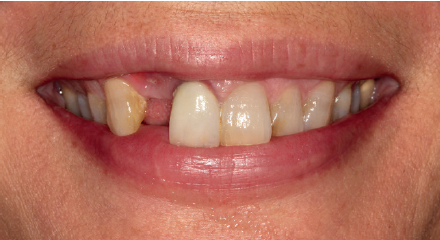

Tres meses después, se comienza con la fase protésica. El estado del tejido gingival es el correcto, aunque a nivel vestibular nos gustaría lograr un descenso del cenit del futuro diente, por lo que se planifica un injerto de conectivo que permita esta conformación de perfil de emergencia más adecuado. El caso se termina con coronas E max a nivel de 1.2 y 1.1, lográndose una sonrisa armónica y completa ente integrada en el resto de la sonrisa, en cuanto a color, emergencia y disposición de los márgenes gingivales (Figuras 14-15). La paciente continua en seguimien o durante años, mantenié dose la estabilidad de la rehabilitación llevada a cabo (Figura 16).